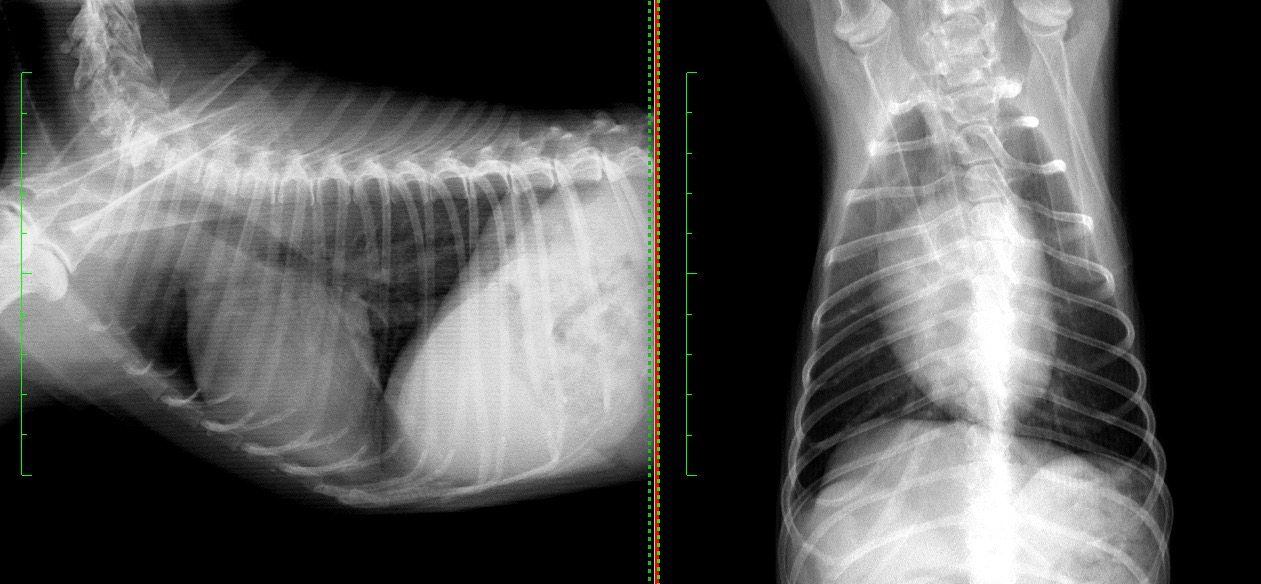

退院時の胸部X線検査では、肺野の不透過性が大きく改善しているのが見て取れます。

退院1週間後の再診時の胸部X線では肺野の不透過性も完全に改善し、呼吸状態はもちろん、元気や食欲などの一般状態も全く問題ない状態でした。